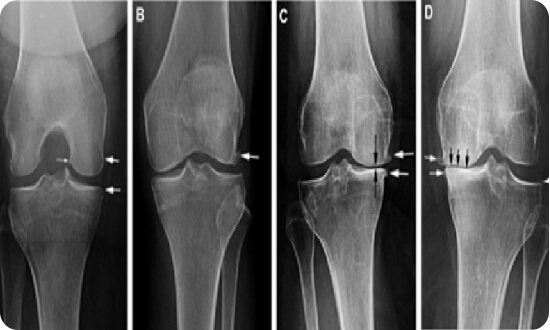

MRI Cơ xương khớp

- H3 coil chuyên biệt lên đến 18 kênh hiện đại nhất miền trung

- Chụp bộ phận nhỏ nhất đến khớp lớn nhất với chất lượng hình ảnh tốt nhất

- Chụp khớp gối 3D, giẩm nhiễu ảnh do bộ phận cấy ghép kim loại gây ra